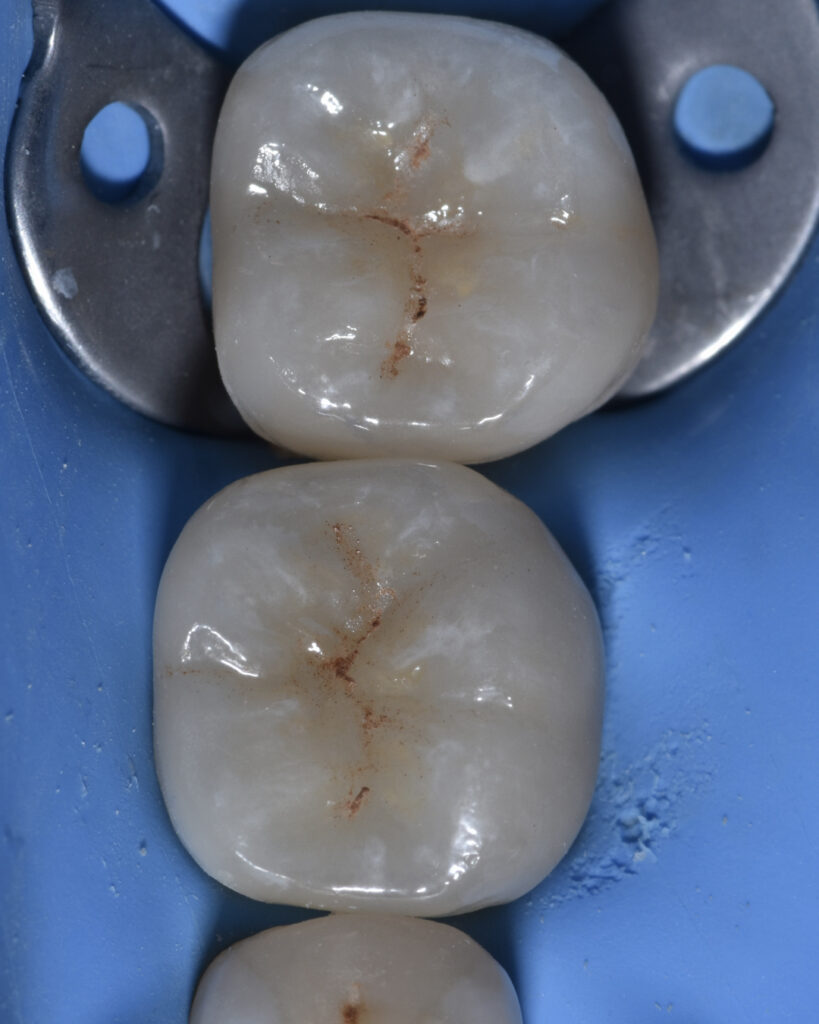

Tooth 3.7 presented a large MOD carious lesion, with both distal cusps and the mesiolingual cusp structurally compromised.